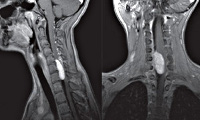

Наиболее безопасным и эффективным способом, позволяющим диагностировать опухоль спинного мозга, выступает МРТ позвоночника. Метод дает возможность послойно визуализировать расположенные в позвоночном столбе мягкотканные образования, проанализировать объем и распространенность опухоли, ее локализацию по отношению к веществу, оболочкам и корешкам спинного мозга, сделать предварительную оценку гистоструктуры новообразования.